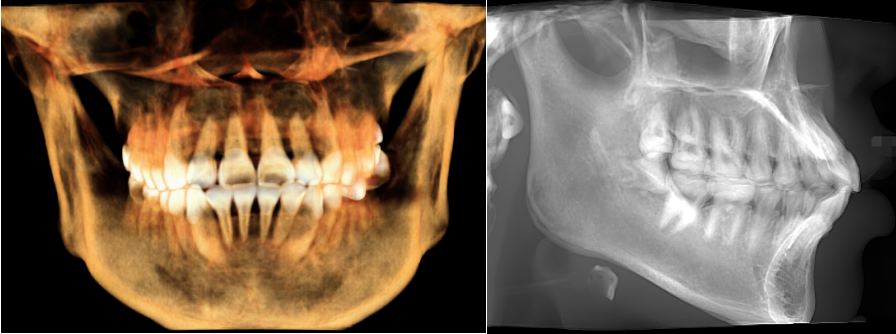

口腔设备有什么一文读懂 | 口腔影像设备大科普,哪种才是最适合你的选择?_https://www.jmylbn.com_新闻资讯_第12张

▲中视野图像

中视野可完整显示全口牙列情况,但无法覆盖双侧颞颌关节和上颌窦全阔的影像,更适用于单颗及多颗牙种植的临床应用,以及上颌窦底、双侧颞颌关节及部分上颌窦轮廓等的观察与诊疗;